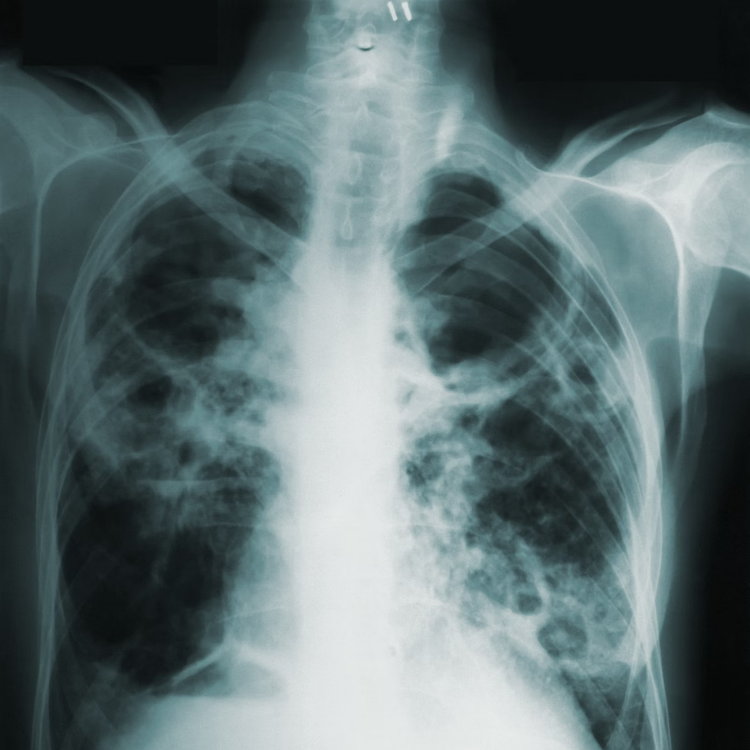

Mr Hector Mahlobo (Pharmacist) and Mr Isaac Ngomane from Aquity Innovations, Unfolding TB Treatment Journey on RISEfm MidMornings Health Talk with Tlotlang Moletsane

1. What is TB treatment journey

2. An overview of a typical treatment journey

3. What is the key component in TB treatment